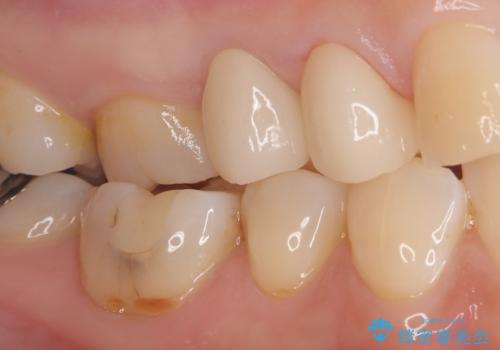

- 患者様は「歯が取れたこと」を主訴に来院されました。

診査の結果、土台ごと脱離しており、歯質の残存量も少ない状態でした。

患者様は歯の保存を強く希望されたため、保存可能な範囲で丁寧に形成を行い、フェルール(歯冠縁下の歯質保持)を確保することを優先しました。

これにより、長期的な被せ物の安定性を目指しました。